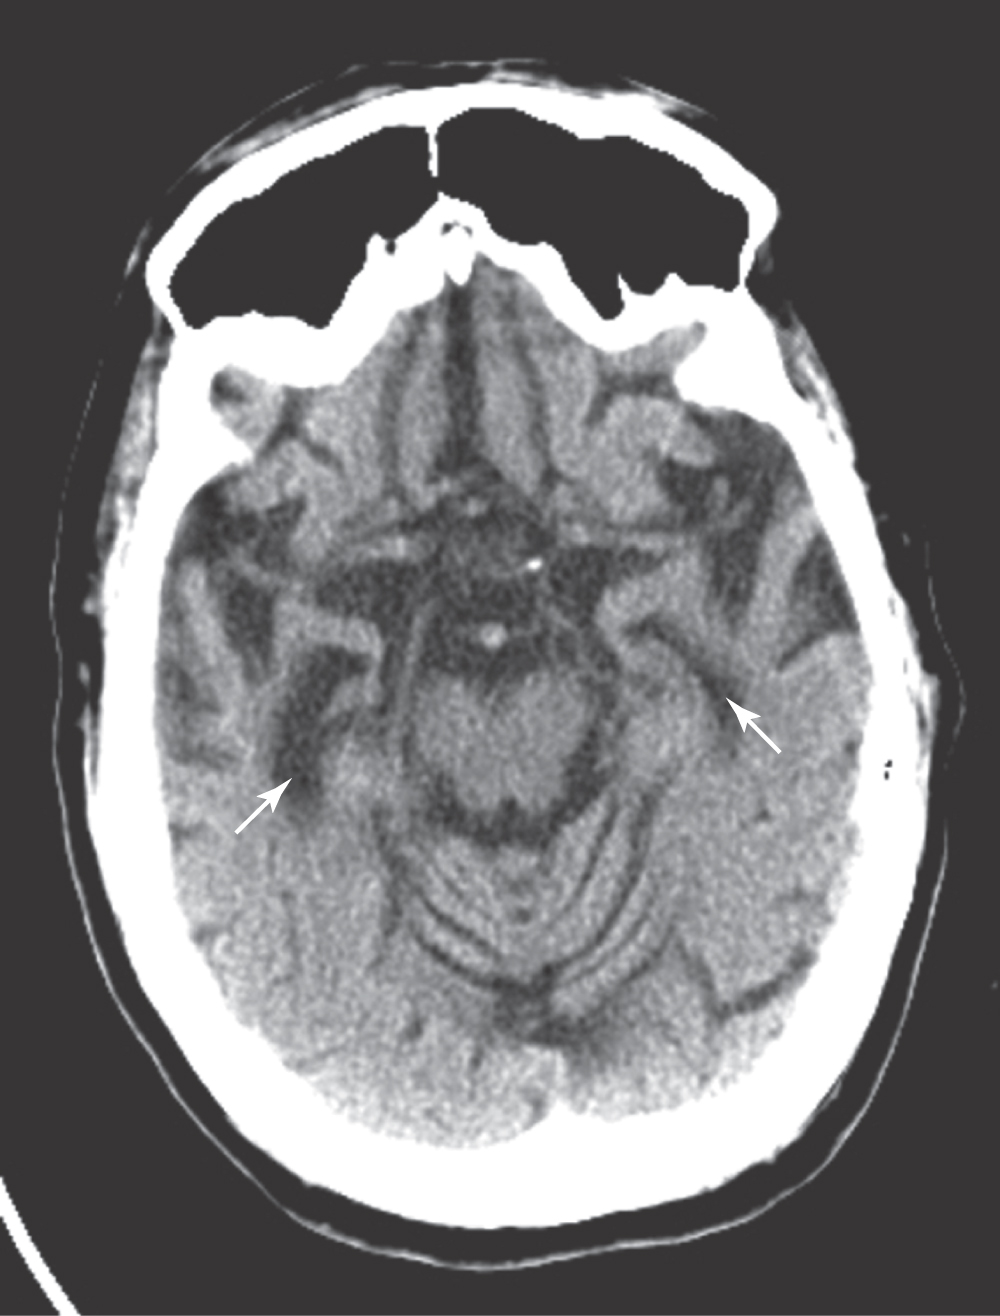

Bilateral damage to the hippocampal formation sometimes occurs in victims of heart attack, near-drowning, or severe hypoglycemia as a result of cerebral ischemia (Fig. 31-6A). The part of the hippocampal formation most vulnerable to anoxia during an ischemic episode is the CA1 area. The CA1-subiculum interface region is referred to as the Sommer sector in pathologic conditions. Affected patients retain memories for events occurring after the ischemic episode. Consequently, they also have difficulty learning new concepts because the new information is not retained (remembered) long enough to become a long-term memory.

Figure 31-6. Axial magnetic resonance image showing hyperintensities in both hippocampi, slightly brighter on the right than on the left, due to severe hypoglycemia (A). In B, a T1-weighted axial magnetic resonance image, note the atrophy of both hippocampi with enlarged temporal horns (arrows) and atrophy of the orbitofrontal cortex in a patient with Alzheimer dementia.

Another condition in which loss of memory and cognitive function is particularly obvious is Alzheimer disease (AD). This disease is characterized, in part, by the presence of neurofibrillary tangles, neuritic plaques, and neuronal loss in specific brain regions (Fig. 31-6B). The subiculum and entorhinal cortices are among the first sites in which these abnormalities appear. As a result, the relay of information through the hippocampal formation is impeded. It is believed that this damage is at least partially responsible for the difficulties with declarative memory characteristic of AD. Poor recall of recent events or incorporation of new facts occurs early in AD. Long-term memory impairment and behavioral changes occur in later phases. Procedural or implicit memory, the motor skills for performing tasks, is relatively spared because this type of memory is encoded by the basal ganglia and cerebellum.